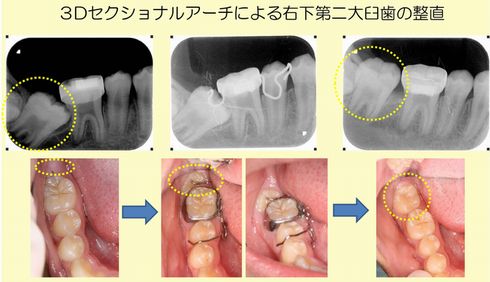

右下の12歳臼歯が斜めになっていてうまく萌出してこない13歳の男の子のプチ矯正の症例です。

右下の12歳臼歯(黄色の点線囲み部)が60°くらい傾いて手前の6歳臼歯に引っ掛かっているため、奥歯のかみ合わせが悪くなっています。患者さんの希望は”できるだけ小さくて目立たない装置でここだけを治して欲しい”ということでした。そこで3Dセクショナルアーチ(下段中央写真)を用いて12歳臼歯をまっすぐに起こすことにしました。約4カ月でうまく萌出させることができました(下段右写真)。